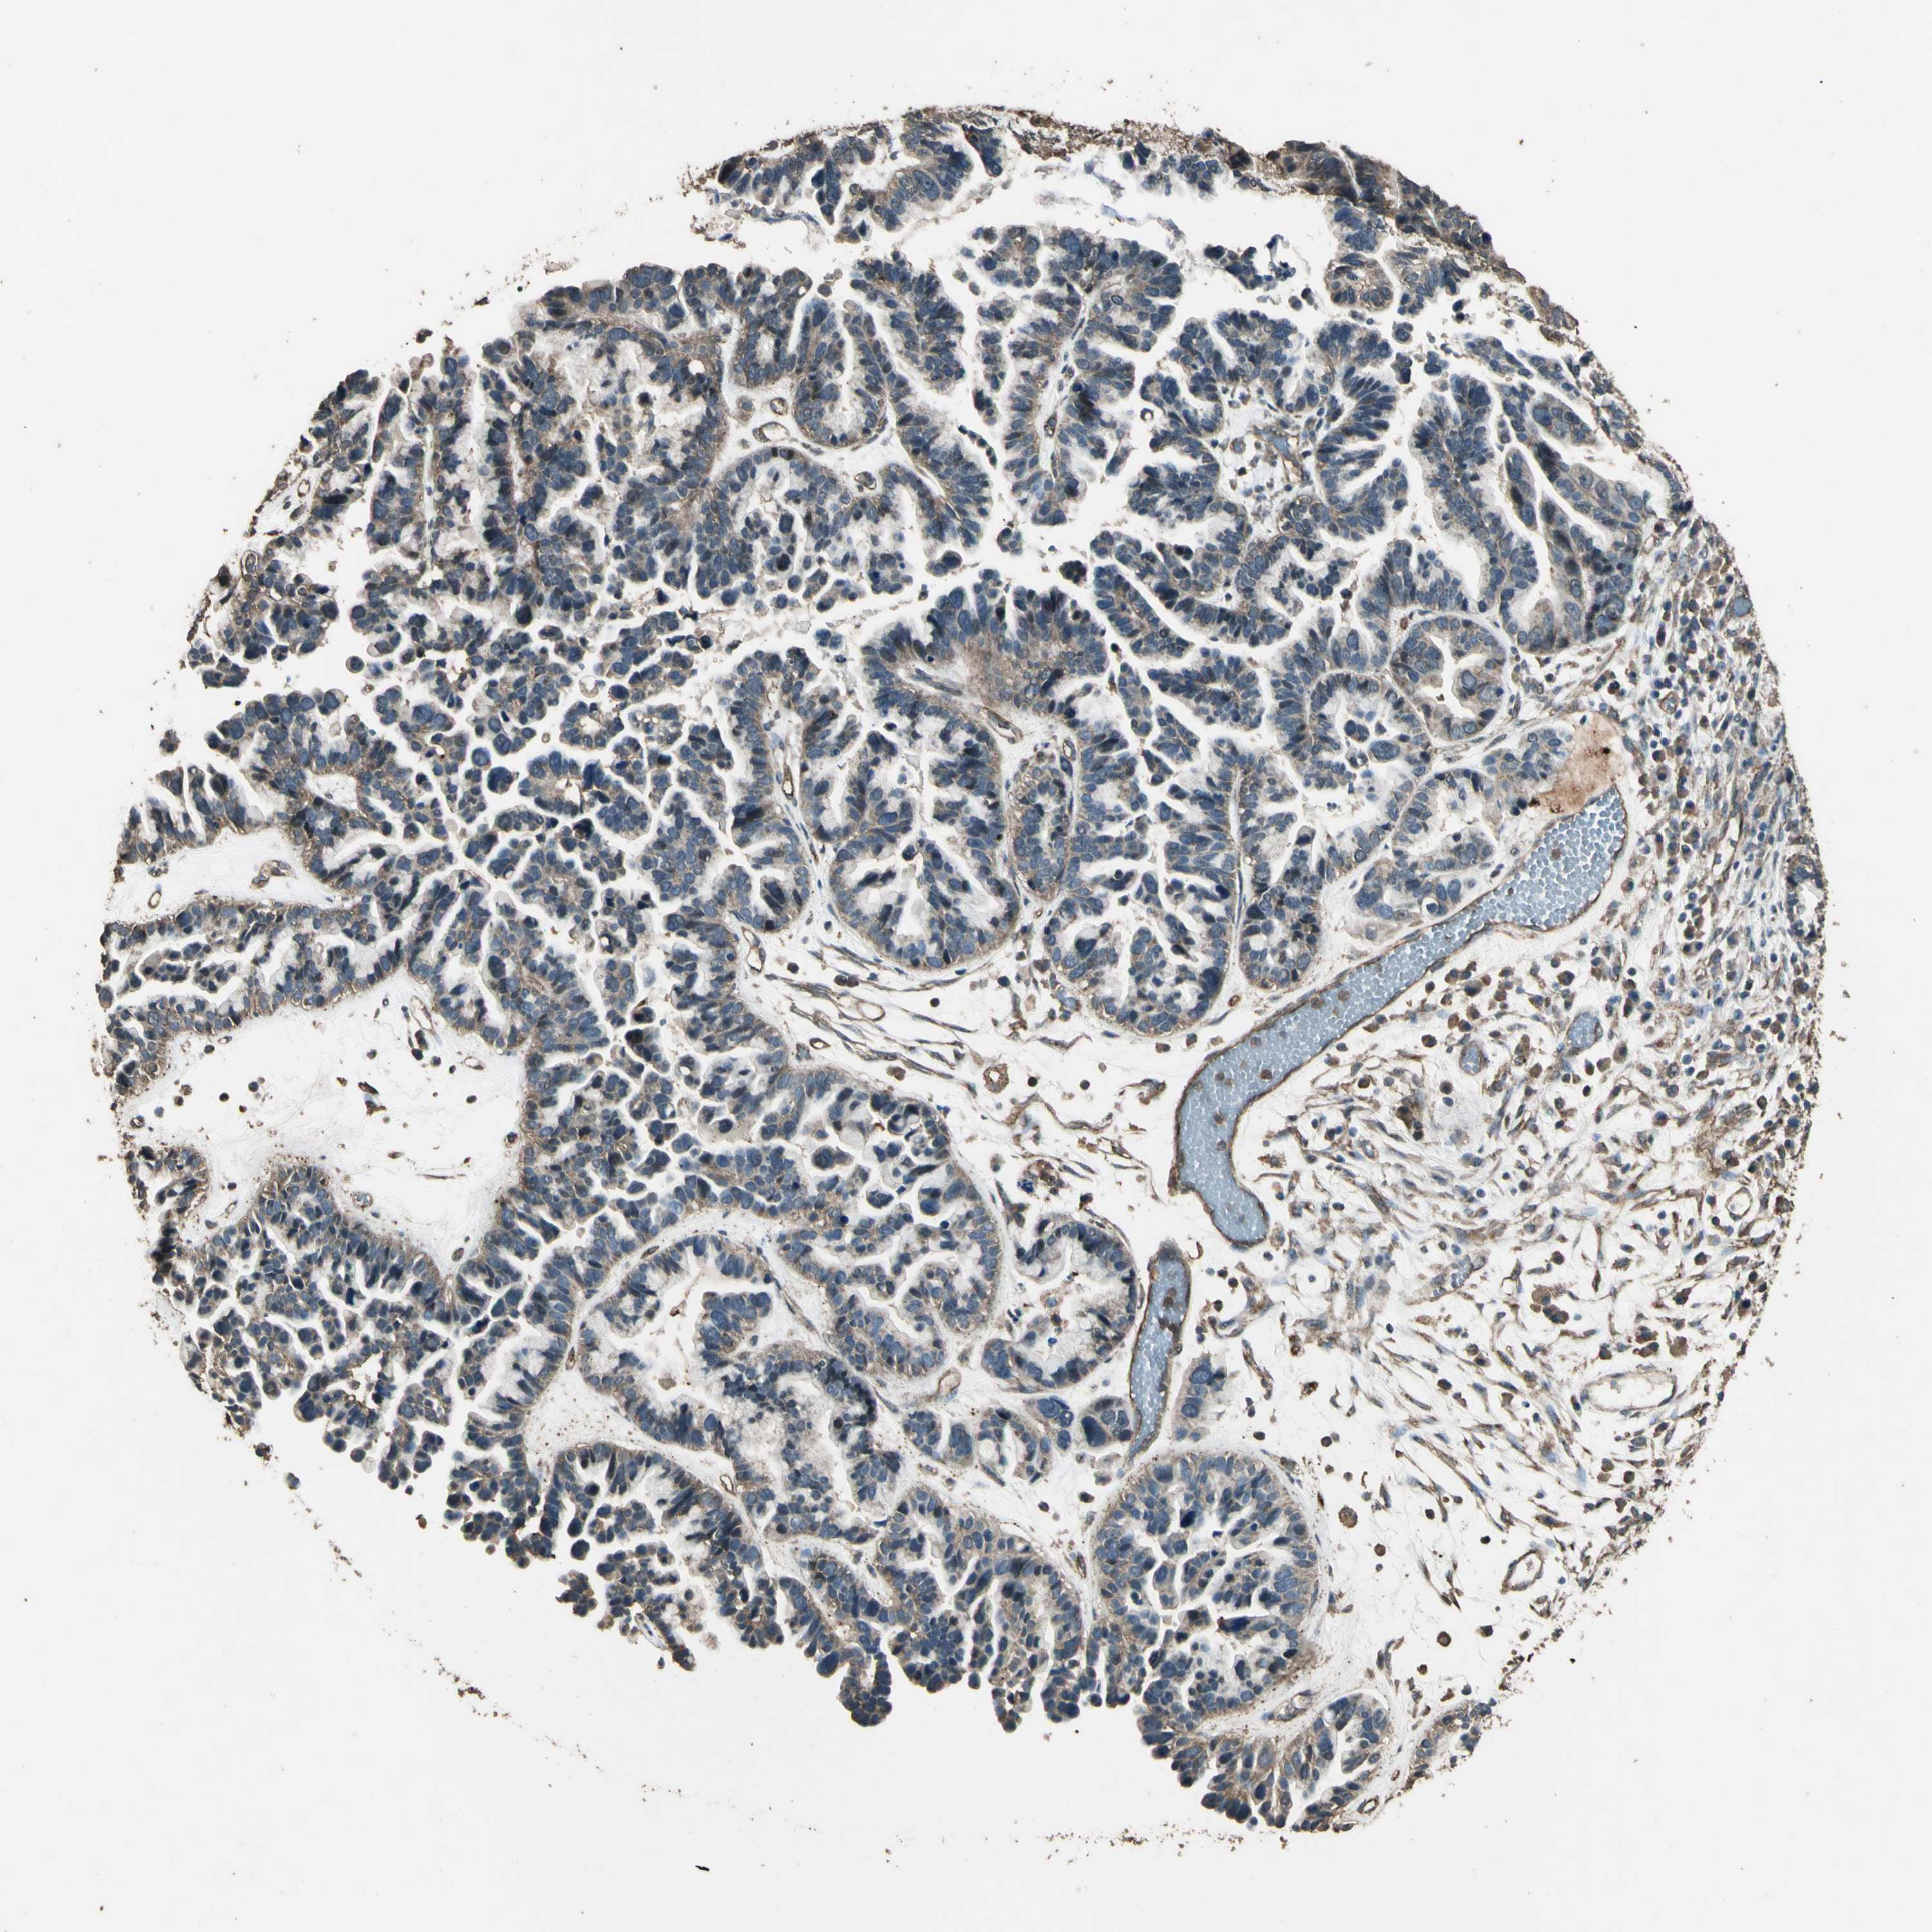

OVARIAN CANCER - Protein expressioni

A mouse-over function shows sample information and annotation data. Click on an image to view it in a full screen mode. Samples can be filtered based on level of antibody staining by selecting one or several of the following categories: high, medium, low and not detected. The assay and annotation is described here.

Note that samples used for immunohistochemistry by the Human Protein Atlas do not correspond to samples in the TCGA dataset.

Antibody stainingi

Antibody staining in the annotated cell types in the current human tissue is reported as not detected, low, medium, or high, based on conventional immunohistochemistry profiling in selected tissues. This score is based on the combination of the staining intensity and fraction of stained cells.

Each image is clickable and will lead to virtual microscopy that enables deeper exploration of all samples and also displays staining intensity scores, fraction scores and subcellular localization as well as patient and tissue information for each sample.

Antibody CAB011232

Staining

High

Medium

Low

Not detected

Intensity

Strong

Moderate

Weak

Negative

Quantity

>75%

75%-25%

<25%

None

Location

Nuclear

Cytoplasmic/membranous

Cytoplasmic/membranous,nuclear

Cystadenocarcinoma, serous, NOS

Carcinoma, endometroid

Cystadenocarcinoma, mucinous, NOS

Carcinoma, NOS